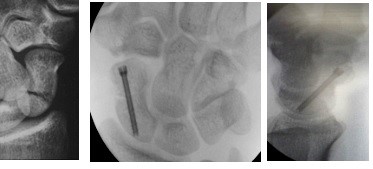

Wrist fractures like percutaneous headless screw fixation for scaphoid

3.Bhat AK, Shetty S, Acharya AM. Cancellous compression bone grafting using headless screw as a strut in scaphoid nonunion by a single volar approach. European Journal of Orthopaedic Surgery & Traumatology. 2023 Feb :1-10.